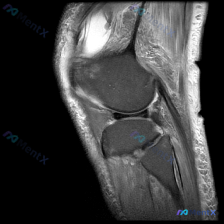

刚整理了一份有意思的影像读片病例,和大家分享一下思路。 病例基本信息 本次仅提供放射影像-膝盖MRI-T1序列-矢状位单张图像,核心问题是询问图像中是否存在半月板异常。 影像学读片结果 我仔细读了这张片子,所有结构的情况如下: 1. 骨骼结构:股骨远端、胫骨近端、髌骨的骨皮质连续,骨髓信号正常,没有...

病例读片:主诉半月板异常,但这张MRI没看到明显问题? 整理了一份有意思的膝关节MRI读片病例,核心矛盾是临床提示半月板异常,但单张影像没找到对应病变,分享一下分析思路。 --- 病例基本影像信息 这是一张膝关节矢状位MRI单张切片,不是用户最初提到的肘部影像。 影像基础评估 - 定位:膝关节矢状位...

看到这个病例挺有代表性,整理了完整的分析思路分享给大家。 病例与影像基础信息 这是一份单张膝关节矢状位MRI影像,临床关注点是"半月板异常",需要基于现有影像做分析。 影像的核心征象整理如下: 1. 序列与定位:膝关节中部偏内侧矢状位,考虑为PDWI或T1加权像,适合显示半月板、韧带解剖结构 2....

刚整理了一份很有临床参考意义的病例读片资料,分享一下思路,大家一起讨论。 病例基本信息 临床关注点:患者自述/临床怀疑存在半月板异常,提供单张膝关节MRI T1序列矢状位图像供分析。 影像读片结果 先把读片的核心结果整理出来: 1. 图像与解剖:图像对比度良好,为膝关节矢状位T1序列,可清晰显示股骨...

看到一个很典型的临床-影像矛盾病例,整理出来和大家分享思路。 病例核心信息 这是一张膝关节矢状位MRI单张图像,临床关注点为「半月板异常」,我们先来看影像的全面评估结果: 1. 骨骼结构:股骨远端、胫骨近端、髌骨轮廓完整,无明显骨皮质中断或骨折 2. 关节软骨:股骨、胫骨关节面软骨信号均匀,无明显剥...